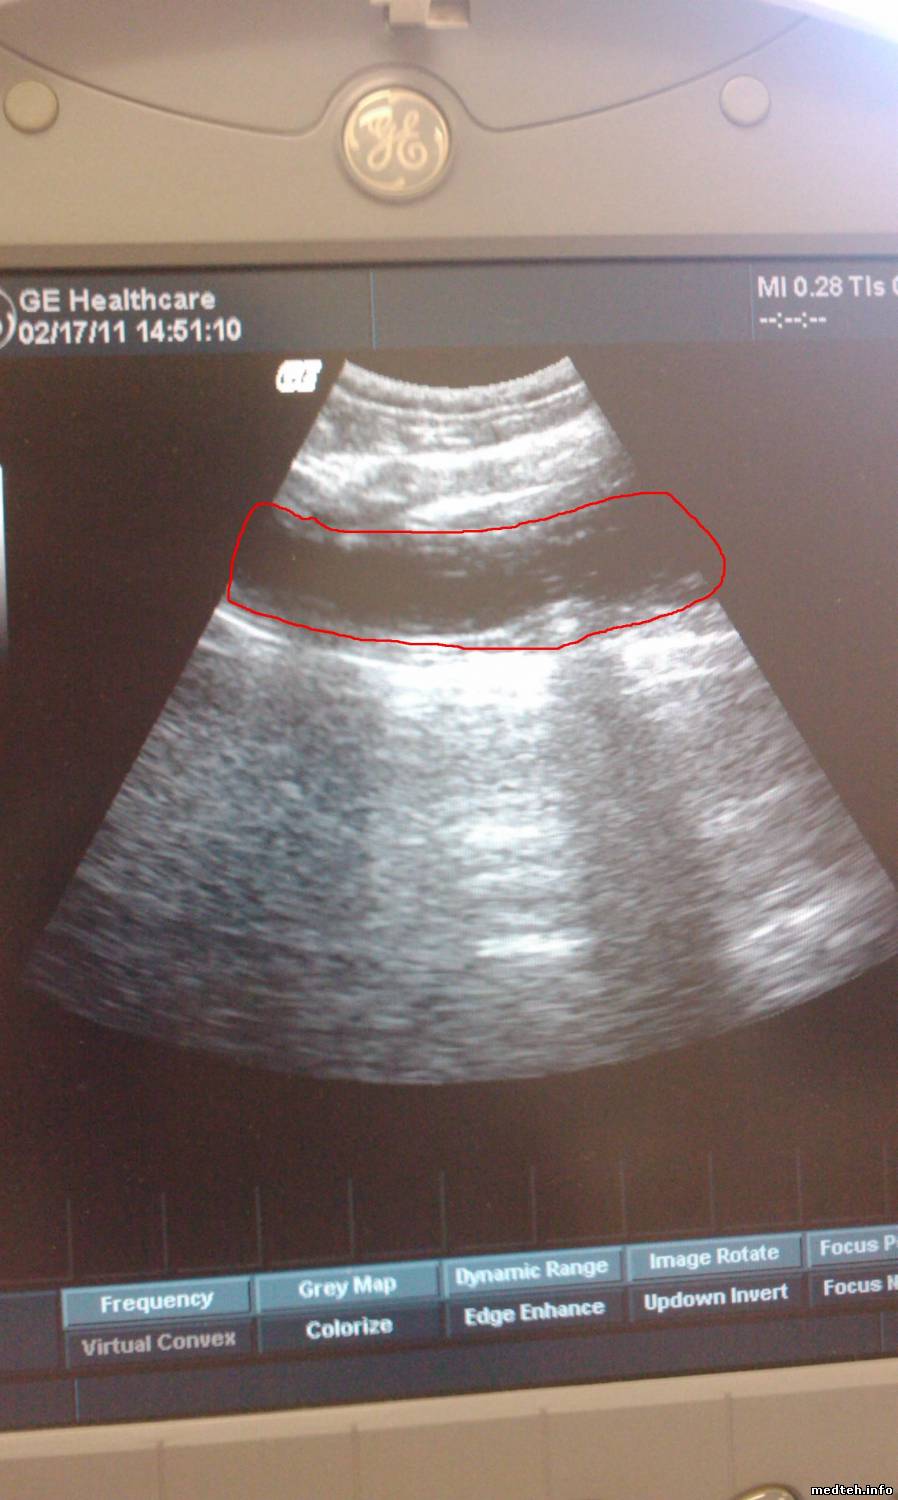

TritonДата: Четверг, 17.Фев.2011, 08:00 | Сообщение # 173

Наконец то я смог сделать фотографии... На фотографии красным обведена темная область, которая смущает врачей. Я не специалист в УЗИ даже и не знаю чей это глюк: датчика, программы, настроек

DenkotДата: Четверг, 17.Фев.2011, 08:14 | Сообщение # 174

Картинка ну точь-в-точь как если бы один из движков TGC сдвинули до упора влево...

покопайте пока в ту сторону.

- проверить движки

- подвигать движки и проверить, адекватно ли работает каждый. Может, какой-то не реагирует?

- если ничего не помогает, открыть аппарат и проверить все разъемы клавиатуры, обращая внимание на TGC, передернуть эти разъемы

При разборке снимается клава, отсоединяется разъем, возможно просто при сборке контакт не прижался

Проверьте все это пока что.

Потому что если это не TGC, то это уже хуже...

перед тем как разбирать, обязательно (!) пошевелите движки и посмотрите, все ли работают и как

если один не работает или работает не так, то это TGC

я все-таки думаю, что это оно - уж больно типичная картина

покрутил все датчики TGC. Каждый из них отвечает за свою область на экране, делает ее более темнее или более светлее... второй сверху датчик ( примерно он и отвечает за темную область, которая обведена на рисунке реагирует довольно странно... он не меняет темную область, он меняет все картинку... причем четко до половины движения датчика, т.е. движемся датчиком слева на право: до середины вообще нет изменений, после середины меняется вся картинка

причем все остальные датчики при движении влево делают картинку более светлее, а этот наоборот темнее